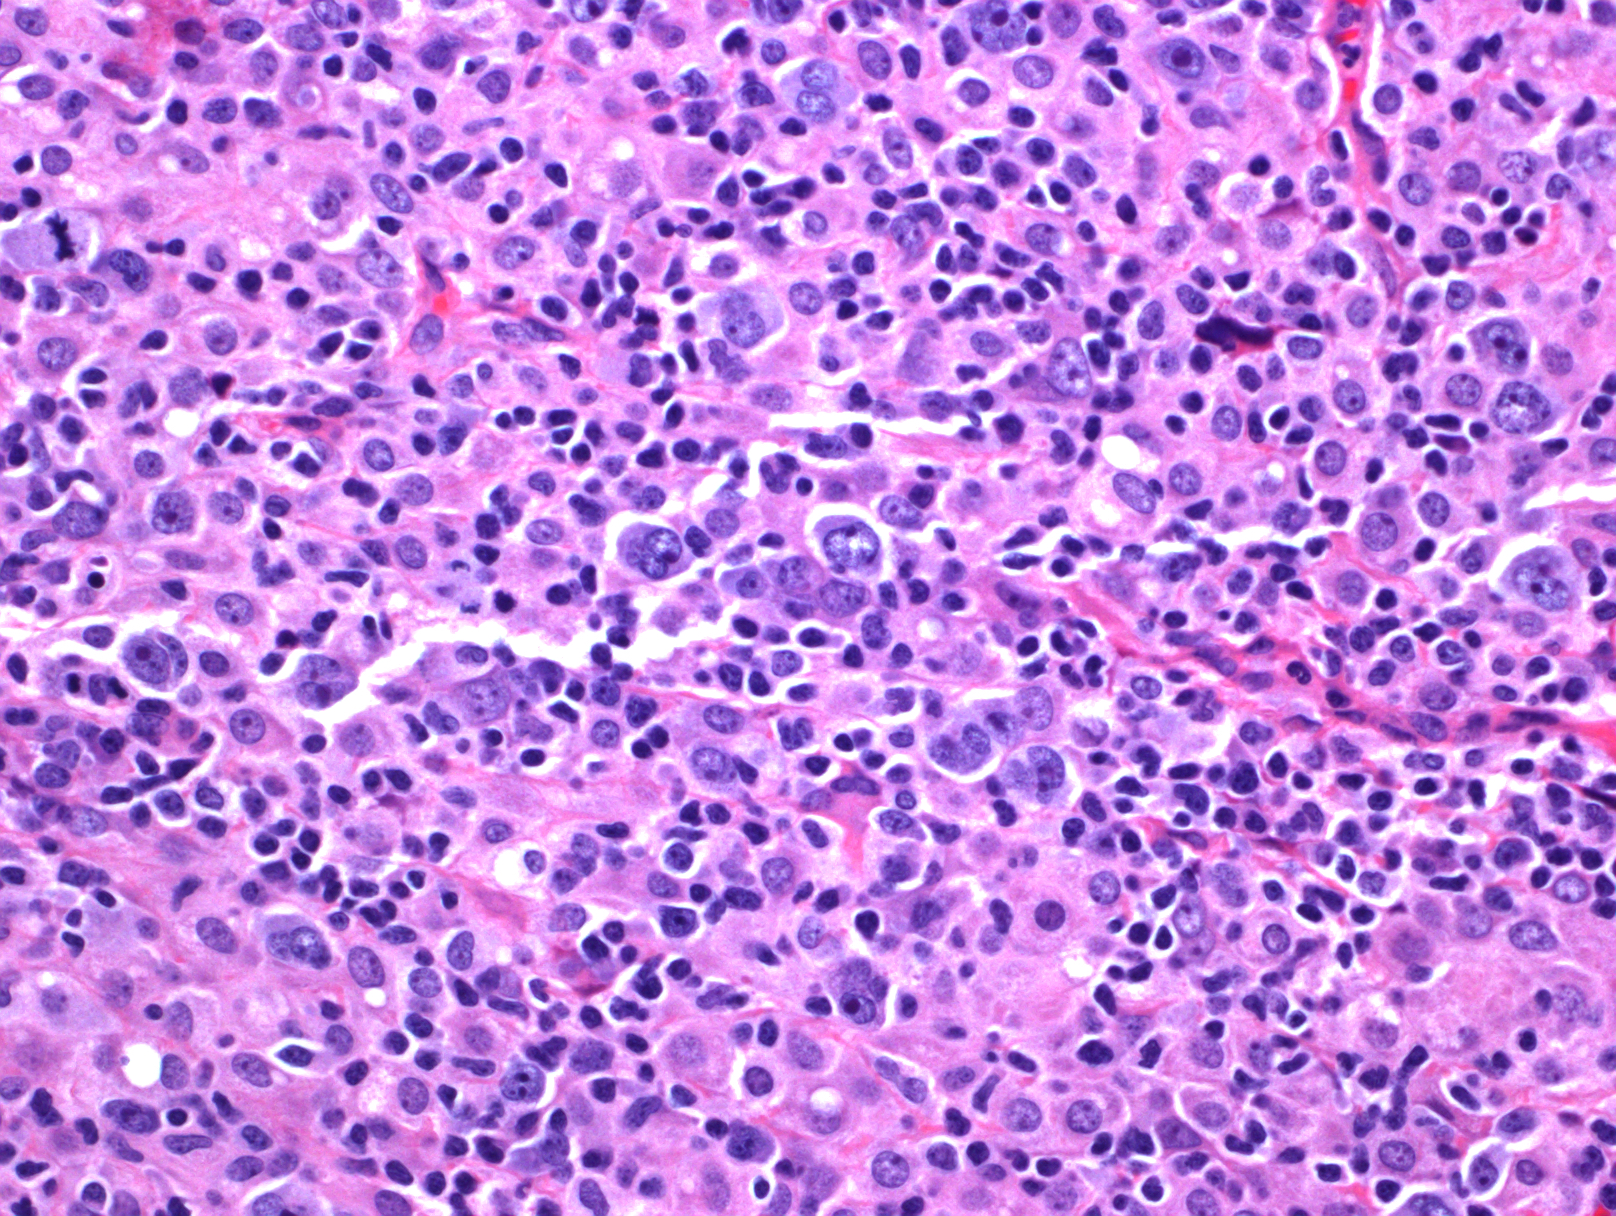

- 肿瘤细胞弥漫浸润,正常组织或淋巴结结构完全破坏,常伴凝固性坏死。

- 肿瘤细胞型态类似中心母细胞、免疫母细胞,浆母细胞、Reed-Sternberg 样细胞或呈现多形性细胞。老年多累及结外组织,常表现两种形态亚型:(1)多形态亚型:肿瘤细胞中混有大量反应性细胞如小淋巴细胞、组织细胞和浆细胞;(2)大细胞亚型:成片大肿瘤细胞。年轻人多累及淋巴结,常表现为三种形态亚型:(1)T/组织细胞丰富型大 B 细胞淋巴瘤样;(2)灰区淋巴瘤样(介于典型霍奇金淋巴瘤和弥漫大 B 淋巴瘤之间);(3)弥漫大 B 淋巴瘤(非特指)样。以上亚型的确定虽有助诊断,但有一定主观随意性,不是必需的。